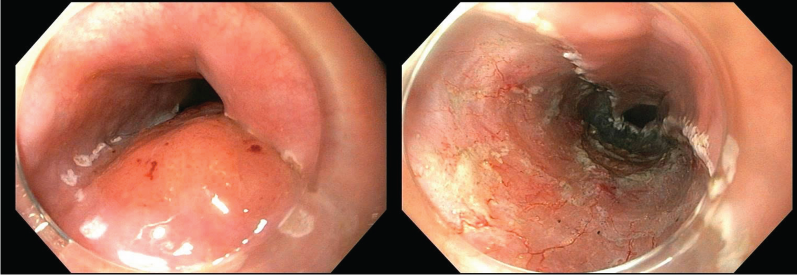

Kết quả EUS cho thấy tổn thương là một cấu trúc giảm âm, nằm ở lớp niêm mạc, trong khi đó lớp hạ niêm mạch còn tương đối nguyên vẹn. Chính vì thế, quyết định can thiệp ESD đã được đưa ra.

Tiến hành can thiệp ESD và kết quả

Trình tự thực hiện ca ESD:

- Đánh dấu: Dual knife

- Tiêm nâng: Non-lifting sign (-)

- Cắt vòng: Dual knife Cut 2 30W

- Phẫu tích dưới niêm mạc: Dual knife Cut 2 30W + Force coag 30W

- Cầm máu: Soft coag 40W

- Nguồn cắt đốt: Olympus ESG 100

- Thời gian can thiệp là 60 phút.

Kết quả can thiệp ESD:

- Carcinoma vảy không sừng hóa, mô u xâm nhập lớp niêm mạc đệm

- pT1a-LPM, v0,ly0, HM0,VM0

- Hướng xử trí tiếp theo: Theo dõi